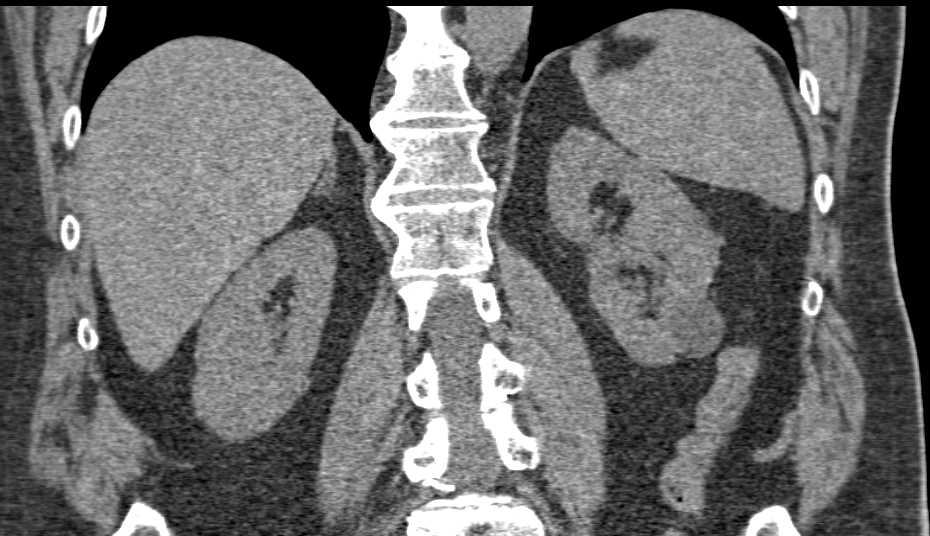

Necrotic Bladder Cancer in Pelvis with Filling Defects Left Renal Pelvis